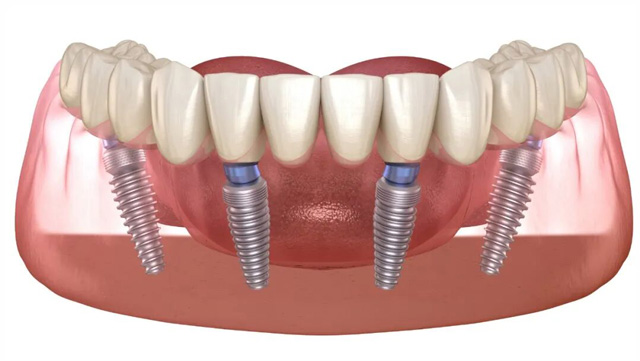

4All-on-4/6 即拔即种

通过4颗或6颗倾斜植入的种植体支撑上下颌整排牙齿,利用前牙区较厚的皮质骨提供初期稳定性,避开后牙骨量不足区域。适用于半口/全口缺牙患者。